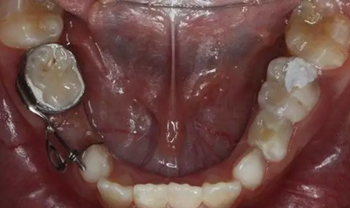

1、 患者 男 7歲 右下乳IV因齲早失

40、加力后,重新就位合面觀

42、牙面拋光,試合制作好的間隙恢復(fù)器,將曲簧水平部分形成與牙面弧形一致,羧酸鋅水門汀粘結(jié)固定

43、粘結(jié)后的頰面觀

44、8周后復(fù)診間隙推開,自動變換為間隙保持器